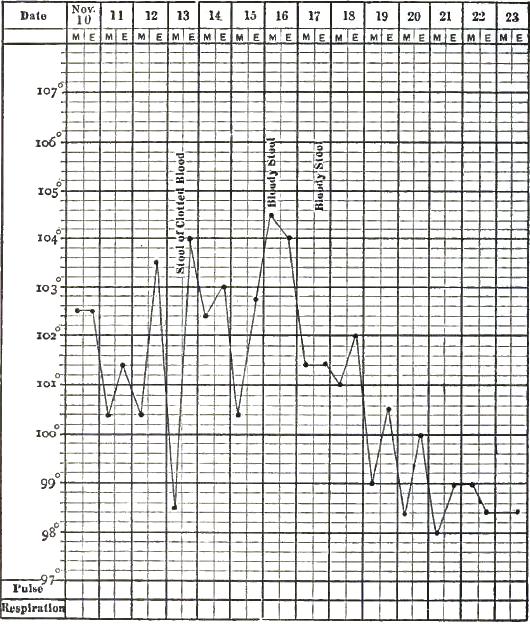

| 12. | CHART OF TYPICAL RANGE OF TEMPERATURE IN TYPHOID FEVER, AFTER WUNDERLICH |

| 13. | CHART SHOWING RECRUDESCENCE OF FEVER FROM INDISCRETION OF DIET |

| 14. | CHART SHOWING FALL OF TEMPERATURE FROM INTESTINAL HEMORRHAGE IN TYPHOID FEVER |

| 15. | PULSE-TRACING IN RELAPSES OF TYPHOID FEVER |